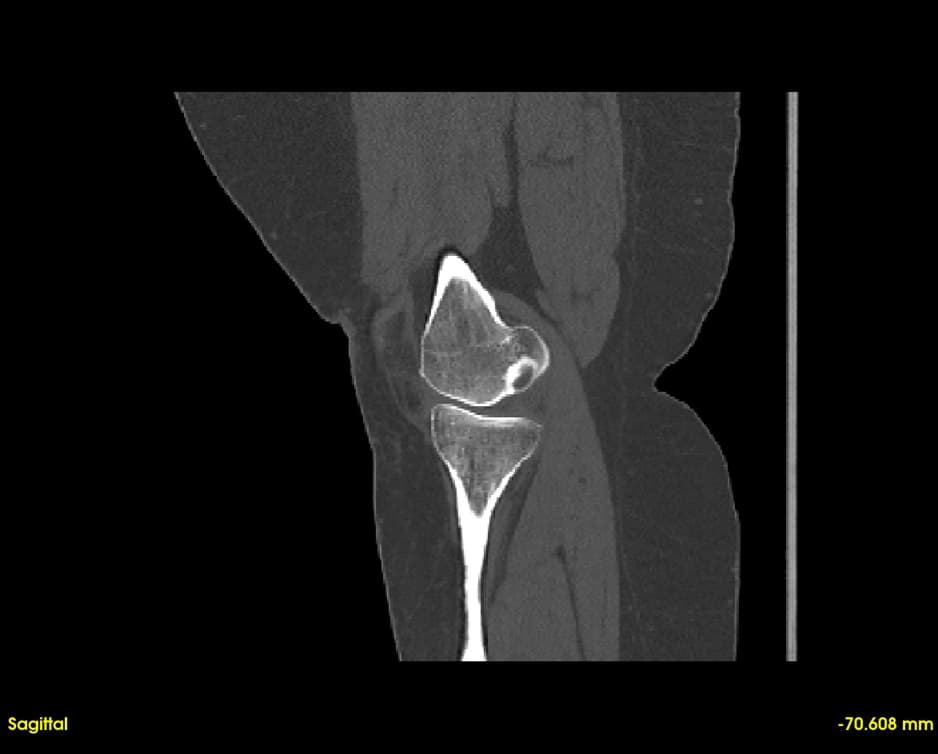

Simultaneous axial, sagittal, and coronal views. Navigate through slices with synchronized cross-referencing.

Explore slices with multi-planar reconstruction views

Segment bones, vasculature, and soft tissues with precision. User-friendly tools for accurate anatomical boundary delineation.